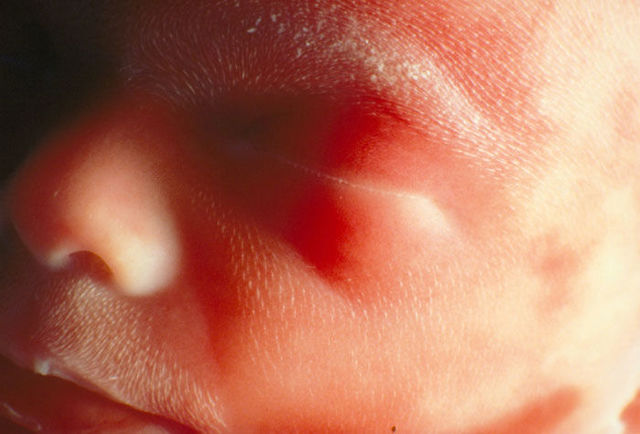

• Semana 7

Semana 7

Durante esta semana se forman los párpados. El embrión se observa con una cabeza grande pero la barbilla es pequeña aún. En estos días en cuando las células entre los dedos entran en apoptosis y entonces se forman los surcos interdigitales. Ya se puede ver que el embrión está nadando en su saco amniótico a pesar de que aún no llega a las 2 cm de longitud. En esta semana también se forma el tubérculo genital y las membranas urogenital y anal.